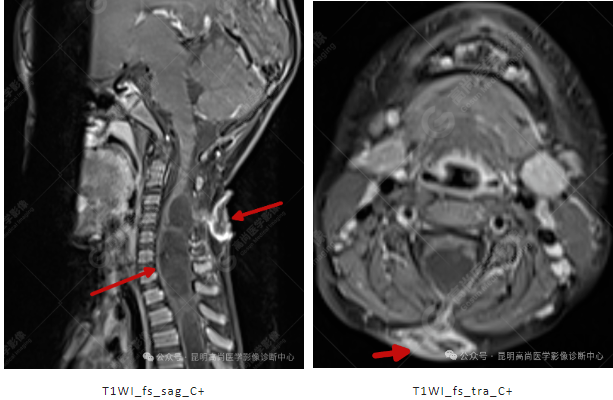

患者女,5 岁,出生时发现颈部包块,大小 3 cm×3 cm,5 年来无变化,拟行手术治疗,要求增强核磁协诊,否认体内金属物,无过敏史。

T1WI_fs_sag_C+

T1WI_fs_tra_C+

影像表现

颈 3-5 层面颈后部软组织不规则片状异常信号影,脊膜膨出可能;颈 3、4 棘突局部显示不清;颈胸髓内(约颈 3-胸 9 椎体水平)异常信号影,考虑囊肿并局部颈髓空洞可能,肿瘤或其他待排;请结合临床及相关检查。